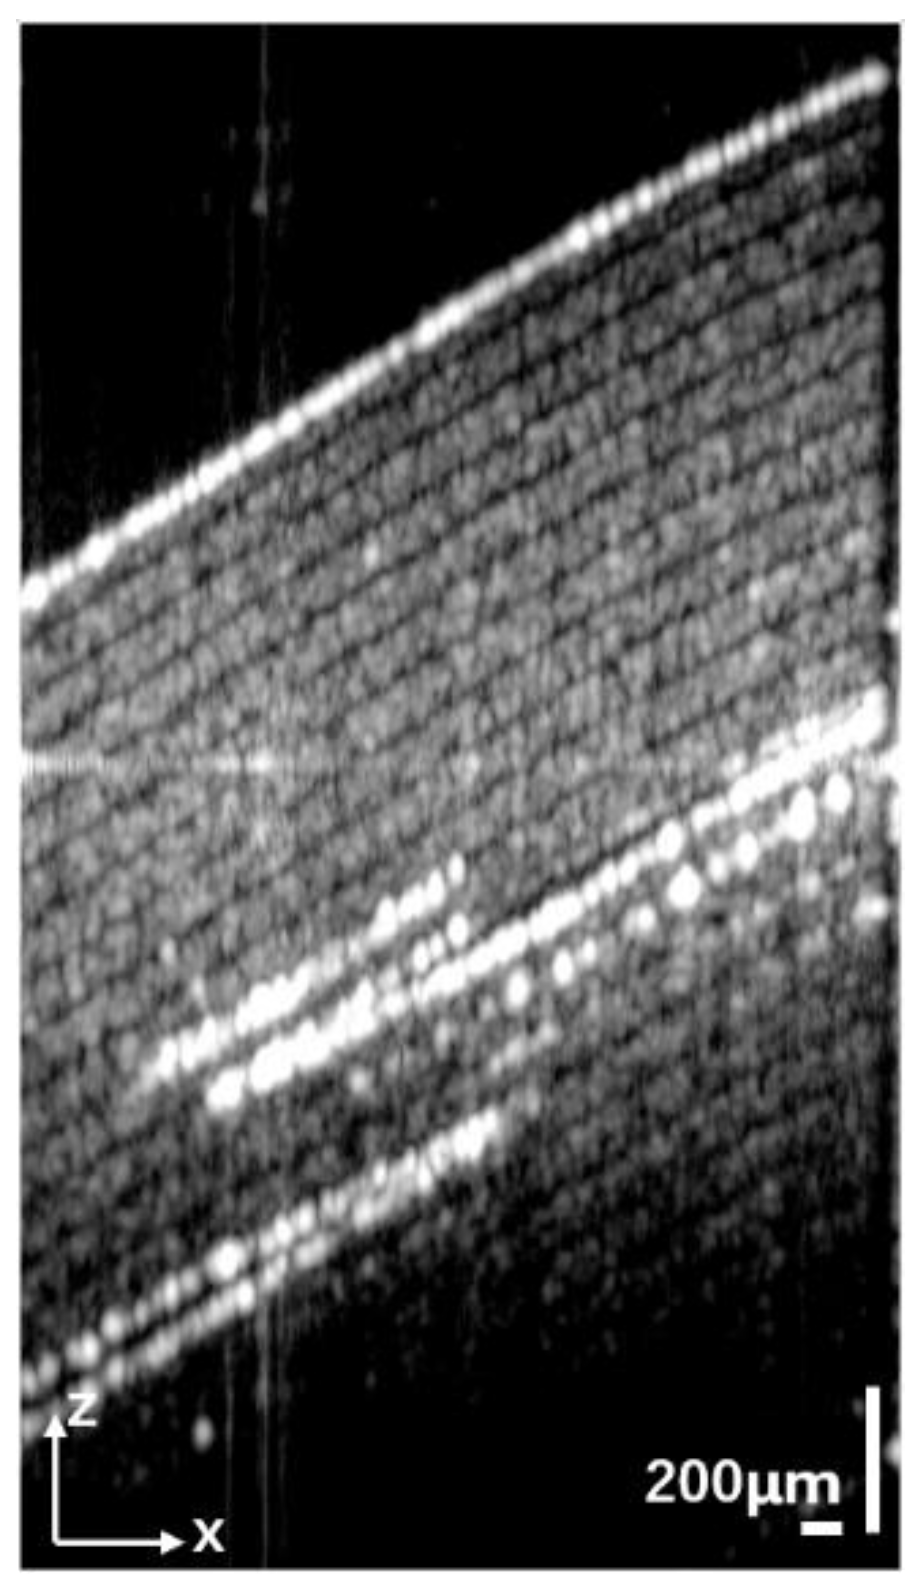

3.3. Pig Thyroid Gland